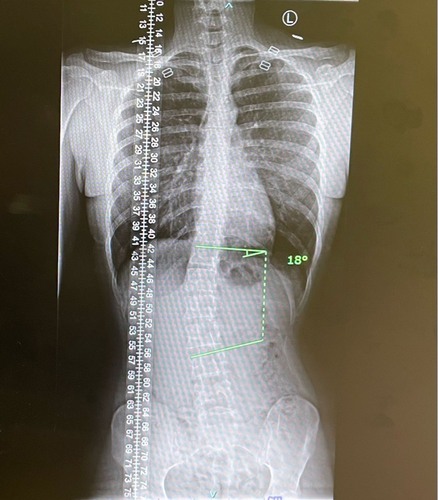

Ik heb ook scoliose. Vroeger in mijn jonge tienerjaren een korset moeten dragen. Vorig jaar heb ik weer foto’s laten maken omdat ik wilde weten in hoeverre dit mijn zwangerschap zou belemmeren, maar gelukkig had ik maar een 18 graden bocht wat ik niet had verwacht. Ik probeer ook zoveel mogelijk mijn rug te versterken dmv krachttraining. Maar mijn bocht is niks vergeleken met die van jullie! Ik hoop dat jullie allen goed de zwangerschap doorkomen🍀 Vooral lekker veel blijven bewegen en oefeningen doen die goed zijn voor je rug 😊